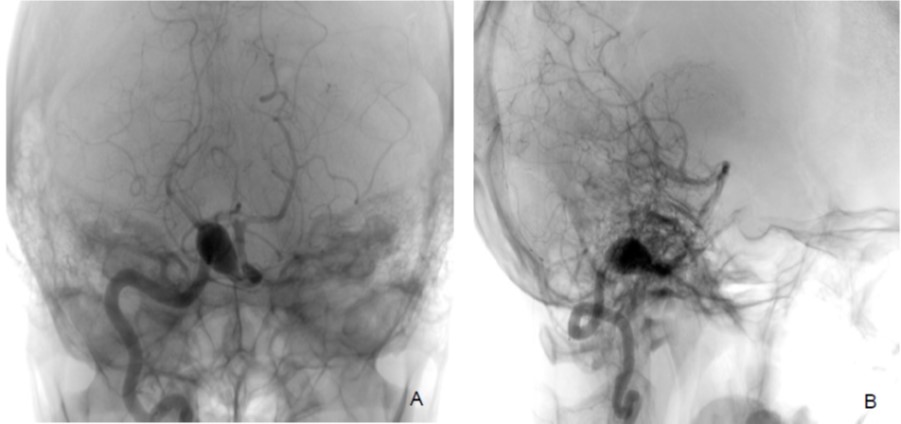

Basilar artery dissection with or without vertebral artery dissection is a rare lesion that can cause intracranial haemorrhage, infarct or mass lesion. We present a case of a middle-aged man with chronic occipital headache and acute hemiparesis. Non-contrasted CT brain shows ectatic right vertebral artery compressing the medulla oblongata and MRI shows acute pontine infarct caused by a basilar artery dissection.